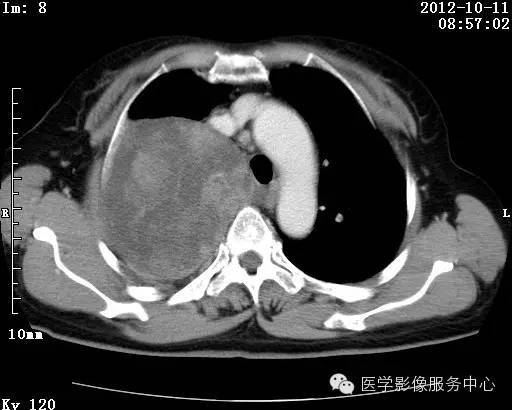

【病例】右肺巨大错构瘤1例CT影像表现

病史:女 65岁咳嗽咳痰 右肺巨大肿块就诊。

错构瘤的主要组织成分包括软骨、脂肪、平滑肌、腺体、上皮细胞,有时还有骨组织或钙化。错构瘤一般为实质致密的球形、卵圆形,也可以是分叶状或结节状,大多数直径在3cm以下。

错构瘤的发病年龄多数在40岁以上,男性多于女性。 绝大多数错构瘤(约80%以上)生长在肺的周边部,紧贴于肺的脏层胸膜之下,有时突出于肺表面。其特征钙化为爆米花样钙化,内有脂肪软骨成分等等。最常见的部位是胸膜下肺实质内,其次为主支气管或肺叶、肺段支气管内。